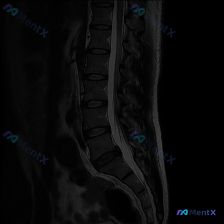

整理了一份网上看到的腰椎MRI病例资料,标注里直接提了“Scoliosis”(脊柱侧弯),但仔细看提供的只有矢状位T2序列。 先把影像核心发现列出来: 1. 椎间盘:各腰椎间盘T2信号普遍减低(黑盘征),提示退变;L4/L5、L5/S1椎间盘后缘明显突出,L5/S1还有向下脱出移位 2. 椎管与神经...

整理到一份腰椎MRI的影像分析资料,最初的问题很直接:「这张图里能观察到脊柱侧弯吗?」 先看已有的影像信息: - 序列:腰椎MRI T2矢状位 - 明确发现:L1/2到L5/S1椎间盘弥漫性脱水低信号,L4/L5、L5/S1向后膨出压迫硬膜囊前缘,部分椎体终板有许莫氏结节,生理前凸存在,序列尚可,无...